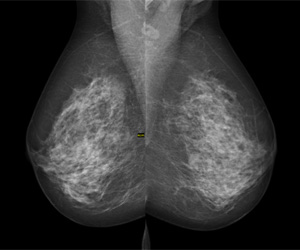

Mammogram image credit (main image): By Rhoda Baer (Photographer) [Public domain or Public domain], via Wikimedia Commons

Digital mammography image credit: © Nevit Dilmen [CC BY-SA 3.0 (https://creativecommons.org/licenses/by-sa/3.0) or GFDL (http://www.gnu.org/copyleft/fdl.html)], via Wikimedia Commons

Interpreting mammograms

My colleagues and I perform image-guided breast biopsies every day. Image-guided biopsies that we perform based on suspicious findings on mammography can yield one of three pathology results: cancer, high-risk, or benign.